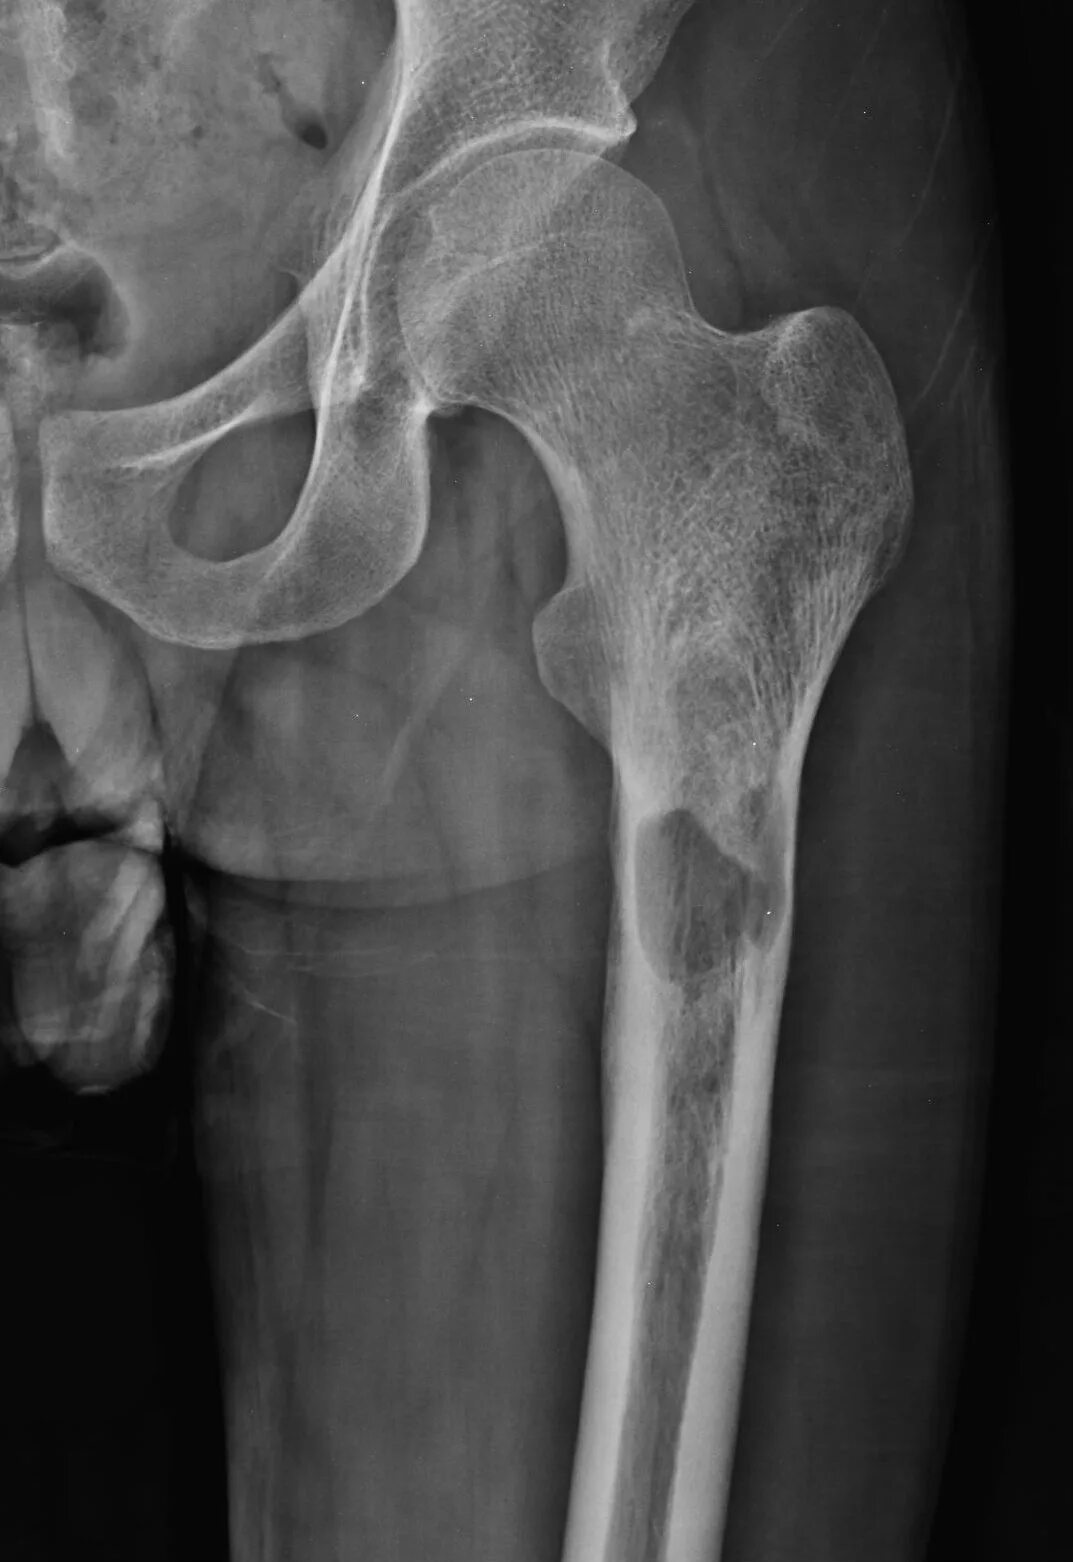

Метастазы в тазобедренном суставе